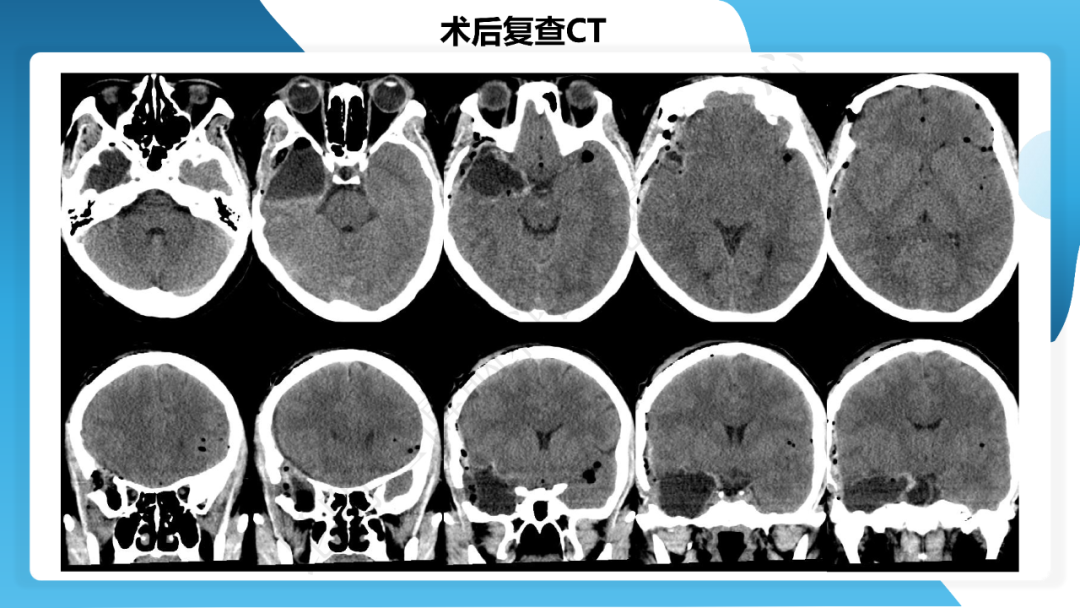

《「痫停」信步》癫痫治疗病例荟萃第三十七期---颞叶海绵状血管瘤相关癫痫的手术治疗一例